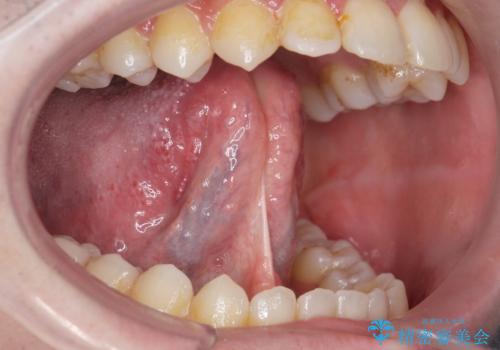

舌の動きの範囲が大きくなり、滑舌が良くなりました。

ラ行も言いやすくなったそうです。

舌小帯の形成術は当日に行うことができます。